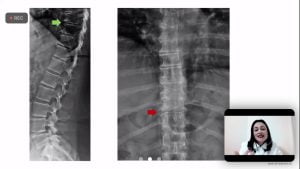

Discussão de casos clínicos: Artrite Psoriásica e iJAK

No dia no 31 de agosto a Sociedade de Reumatologia de Brasília realizou a 3ª Reunião Científica – discussão de casos clínicos. No encontro virtual moderadora Penélope Palominos falou sobre o tema: Artrite Psoriásica e iJAK.